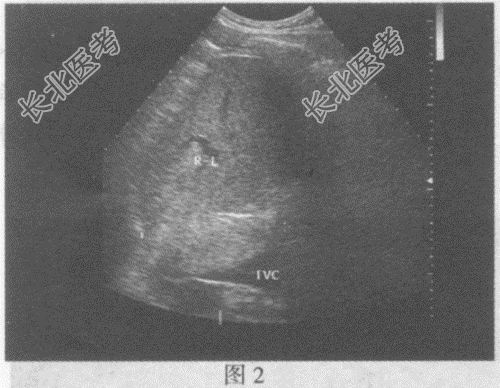

超声综合描述: 右肾失常态,下极可见6.7cm×6.5cm中等回声(图1), 边界尚清晰,内回声欠均匀, 向外突起,CDFI: 内部及周边可见丰富动、静脉血流信号。见彩图。